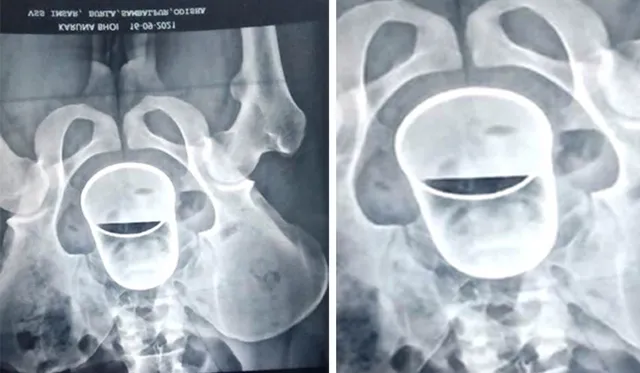

ବଲାଙ୍ଗୀର : ବଲାଙ୍ଗୀର ଜିଲ୍ଲା ଦେଓଗାଁ ଥାନା ରାମଚନ୍ଦ୍ରପୁର ଗାଁରେ ମଦ୍ୟପ ଘଟାଇଥିଲେ ଜଘନ୍ୟକାଣ୍ଡ। ଗାଁର ୧୮ବର୍ଷୀୟ ଯୁବକ କରୁଣା ଭୋଇଙ୍କ ମଳଦ୍ୱାରରେ ଷ୍ଟିଲ୍‌ଗ୍ଲାସ୍‌ ଭର୍ତ୍ତି କରିଦେଇଥିଲେ। ମଦ୍ୟପମାନେ ଏଭଳି ଅମାନବୀୟ କାଣ୍ଡ ଘଟାଇ ଘଟଣାସ୍ଥଳରୁ ଫେରାର ମାରିଥିଲେ। କରୁଣାଙ୍କୁ ବଲାଙ୍ଗୀର ଭୀମ ଭୋଇ ମେଡିକାଲ କଲେଜ ଡାକ୍ତରଖାନାରେ ଭର୍ତ୍ତି କରାଯାଇଥିଲା। ଡାକ୍ତରଙ୍କ ବହୁ ଚେଷ୍ଟା ପରେ ମଧ୍ୟ ଗ୍ଲାସ୍‌ ନବାହାରିବାରୁ ଗତକାଲି ବୁର୍ଲା ଭିମସାରକୁ ପରିବାର ଲୋକେ ନେଇଥିଲେ।

ଶୁକ୍ରବାର ଭିମସାର ସର୍ଜରି ବିଭାଗର ଡାକ୍ତରୀ ଟିମ୍‌ ଏକ୍ସ-ରେ କରାଇବା ପରେ ଅସ୍ତ୍ରୋପ୍ରଚାର କରିଥିଲେ। ଅସ୍ତ୍ରୋପ୍ରଚାର ପରେ କରୁଣାଙ୍କ ମଳଦ୍ୱାରରୁ ଷ୍ଟିଲ୍‌ଗ୍ଲାସ୍‌ ବାହାର କରିବାରେ ସଫଳ ହୋଇଥିଲେ। ଅନ୍ୟପଟେ କରୁଣା କିଂବା ତାଙ୍କ ପରିବାର ପକ୍ଷରୁ ଥାନାରେ ଅଭିଯୋଗ ଦାଖଲ କରାଯାଇନି। ବନ୍ଧପଡ଼ା ପୁଲିସ ନିଜ ପଟୁ ଘଟଣାର ତଦନ୍ତ ଆରମ୍ଭ କରିଥିବା ସୂଚନା ମିଳିଛି। ଗାଁକୁ ପୁଲିସ ଟିମ ଯାଇ ସବିଶେଷ ଘଟଣା ଉପରେ ପଚରାଉଚରା କରିଛନ୍ତି। ତଦନ୍ତ ପରେ ହିଁ ସବୁ କଥା ଜଣାପଡ଼ିବ।